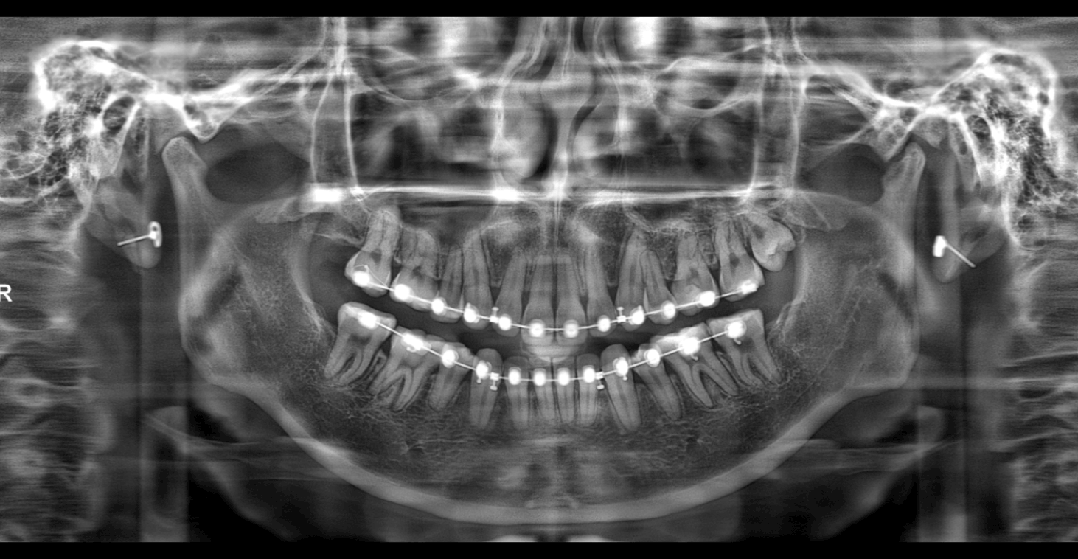

?当前,为解决复杂伪影干扰难题,全新一代“PD-MAR”技术为需求而来,能够高效去除修复填充物、金属冠、种植体等口内高密度物质伪影,同时支持实时对比处理前后影像。

▲“PD-MAR”先进去伪影技术